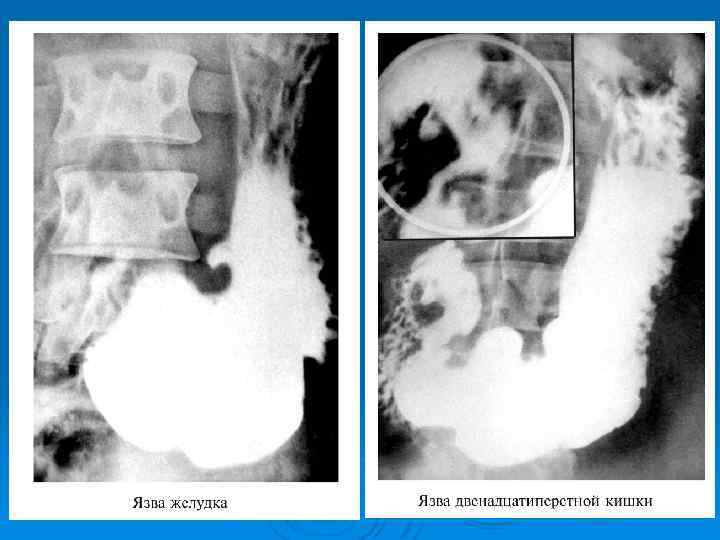

Диагностика: Ø Исследование желудочной секреции l l l базальная секреция соляной кислоты за 1 час в норме 2 5 мэкв стимулированная секреция – 1 20 мэкв за 1 час; соотношение базальной к стимулированной в норме меньше 20% Уровень гастрина и пепсиногена крови Определение наличия Helicobacter pylory Рентгенологическое исследование желудка и 12 п. к. Ø ФГДС Ø Ø Ø

Язва желудка

МАЛИГНИЗАЦИЯ Ø Перерождение в рак является возможным осложнение язв желудка в 15 20% случаев Ø Язвы 12 п. к. не малигнизируются Ø Лечение при угрозе малигнизации хирургическое